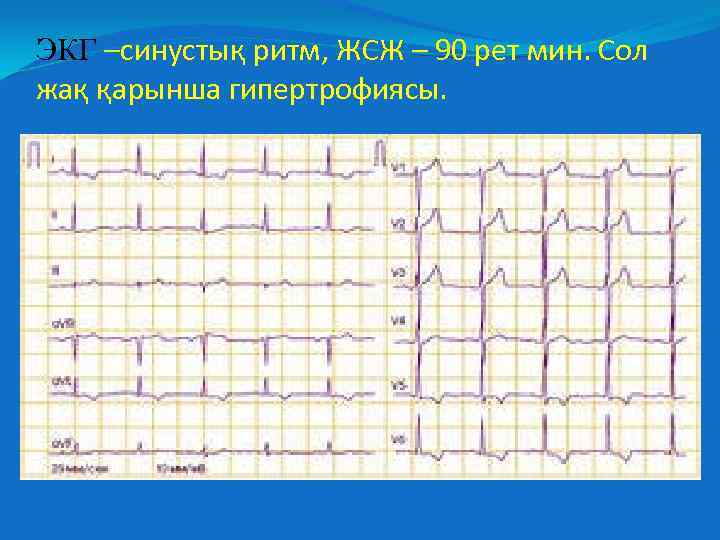

ЭКГ –синустық ритм, ЖСЖ – 90 рет мин. Сол жақ қарынша гипертрофиясы.